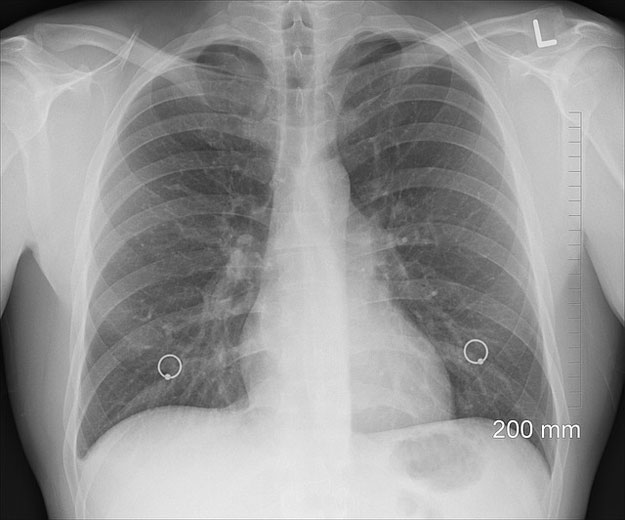

Si l’utilité de la radiographie peut sembler évidente, elle n’est pas sans provoquer des inquiétudes. Revenons ici sur une question courante : la radiographie est-t-elle dangereuse pour la santé ?

Pour voir ce qui n’est pas visible à l’oeil nu, diagnostiquer à temps un mal et mettre en place un traitement. Le dentiste, par exemple, aura recours à la radiographie panoramique dentaire pour vérifier les atteintes aux dents cachées. Nous l’évoquions : la radiographie sert également à dépister les cancers.

Vous l’aurez noté : les campagnes de prévention incitent fortement à la mammographie systématique pour les femmes à risques (âgées de 50 à 74 ans, ou antécédents familiaux par exemple).

Ce n’est pas par hasard : c’est l’examen de référence, qui permet de détecter des cancers de petite taille avant même l’apparition de symptômes, qui indiquent un stade plus avancé de cancer. La radiographie permet également de vérifier des symptômes, éventuellement constatés par palpation, pouvant évoquer un cancer. Une action nécessaire, donc, mais la mammographie n’est pas sans provoquer des débats.